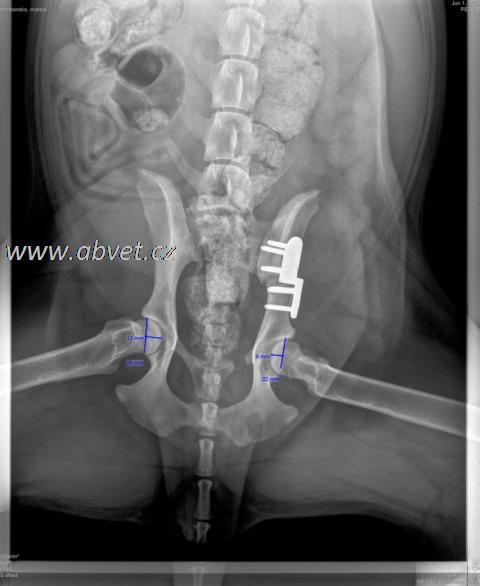

RTG 3 Distraction index (DI)

To zdjęcie jest najistotniejsze w oszacowaniu stopnia rozluźnienia stawu. Według niego mierzony jest wskaźnik DI, który jest wyrażony liczbą i określa odległość środka głowy kości udowej, od środka panewki stawowej.

Za fizjologiczną uważana jest wartość 0 – 0,3, wartości powyżej uznawane są za patologiczne. Im wyższa wartość (powyżej 0,3), tym prawdopodobieństwo wystąpienia HD jest większe.

Pomiar DI - distraction index (zdj.1 DI-0,3 zdj. 2 DI-0,9)

Wartości DI oznaczają:

0 – 0,3 – są fizjologiczne i pies ma minimalne prawdopodobieństwo rozwoju HD

0,3 – 0,4 – wskazują na niskie prawdopodobieństwo rozwoju HD

0,5 – 0,7 – wskazują na umiarkowanie duże prawdopodobieństwo rozwoju HD

0,8 – 0,9 i więcej – wyraźnie wskazują na wysokie prawdopodobieństwo rozwoju HD